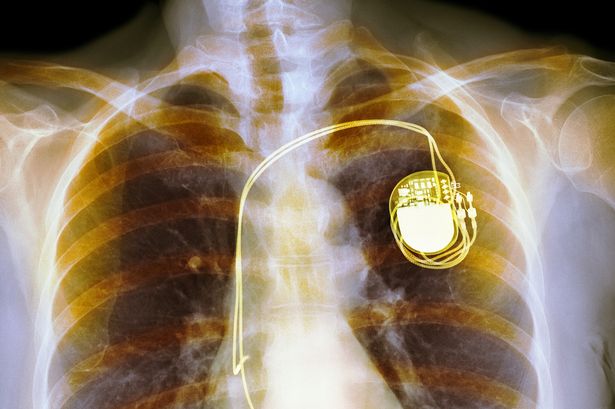

Kalp pili

Aslında bilim insanlarının ilk amacı kalbin sesini kaydetmek için kullanılacak olan bir cihaz geliştirmekti. Zaman içinde bu düşünce hayat kurtaran bir buluş haline geldi.